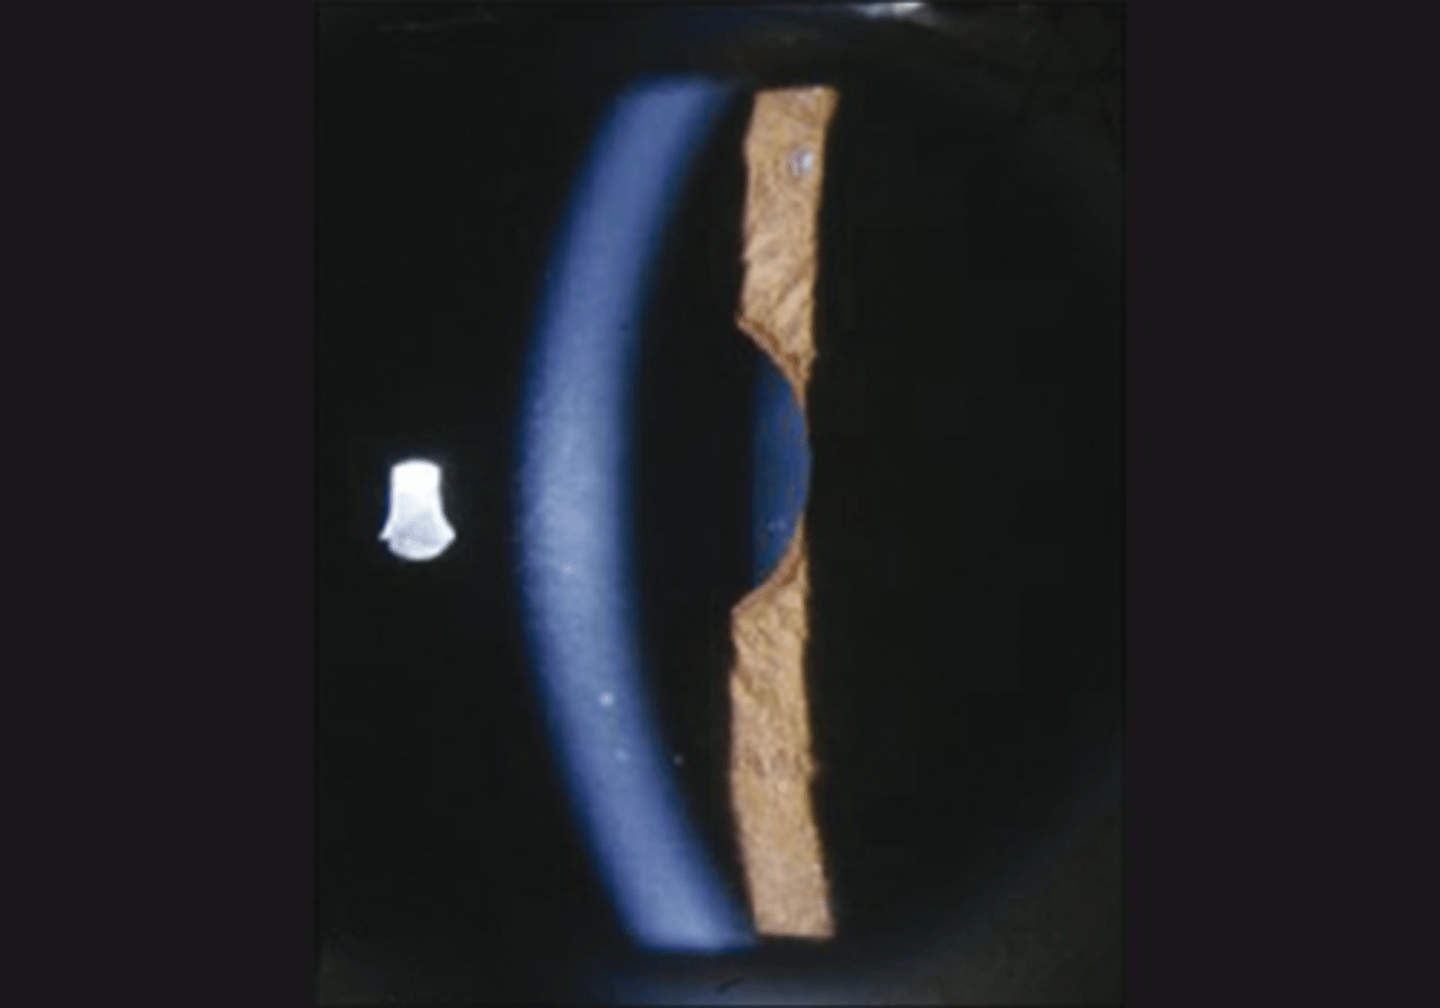

What are the 4 S's that we expect to see when looking at the size and shape of a tonic pupil?

sector paralysis = abnormal shape due to sphincter/dilater paralysis

stromal spread = iris stroma spreads due to lack of innervation

pigment stream entropion = pupil border of iris is entropic adjacent to a part of the pupil border that is more flat

stromal streaming = stroma flows towards area that sphincter still works when light is turned on